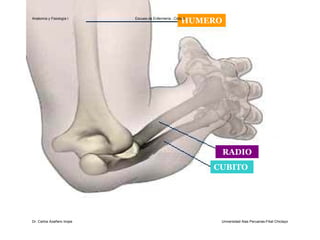

El documento describe la anatomía del antebrazo y la mano. Explica que el antebrazo está formado por el radio y el cúbito, describiendo las características de cada hueso como sus cuerpos, extremidades y superficies articulares. También describe la articulación del codo y los huesos de la mano, incluyendo el carpo, los metacarpianos y las falanges.